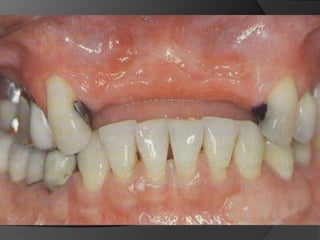

Planificación Del Tratamiento En Restauraciones UnitariasRestauraciones Extracoronarias

Estructura coronaria insuficiente para retener la restauración dentro de la corona del dienteEstructura dentaria defectuosa o socavadaModificar los contornos para mejorar la oclusión o la estética

CORONA DE RECUBRIMIENTO PARCIAL: Corona de deja una o más superficies axiales sin cubrir. Proporciona retención moderada.

CORONA COMPLETA EN METAL: 	En dientes con múltiples superficies axiales defectuosas o destruidas. Proporciona la máxima retención.	La superficie oclusal	favorece  el chequeo oclusal

CORONA COMPLETA METAL-CERÁMICA: Iguales indicaciones que la metálica pero  estética

Planificación Del TratamientoEn Restauraciones UnitariasRestauraciones Extracoronarias

Estructura coronaria insuficientepara retener la restauración dentro de la corona del dienteEstructura dentaria defectuosa o socavadaModificar los contornos para mejorar la oclusión o la estética

CORONA DE RECUBRIMIENTOPARCIAL: Corona de deja una o más superficies axiales sin cubrir. Proporciona retención moderada.

CORONA COMPLETA ENMETAL: En dientes con múltiples superficies axiales defectuosas o destruidas. Proporciona la máxima retención. La superficie oclusal favorece el chequeo oclusal

CORONA COMPLETA METAL-CERÁMICA:Iguales indicaciones que la metálica pero estética